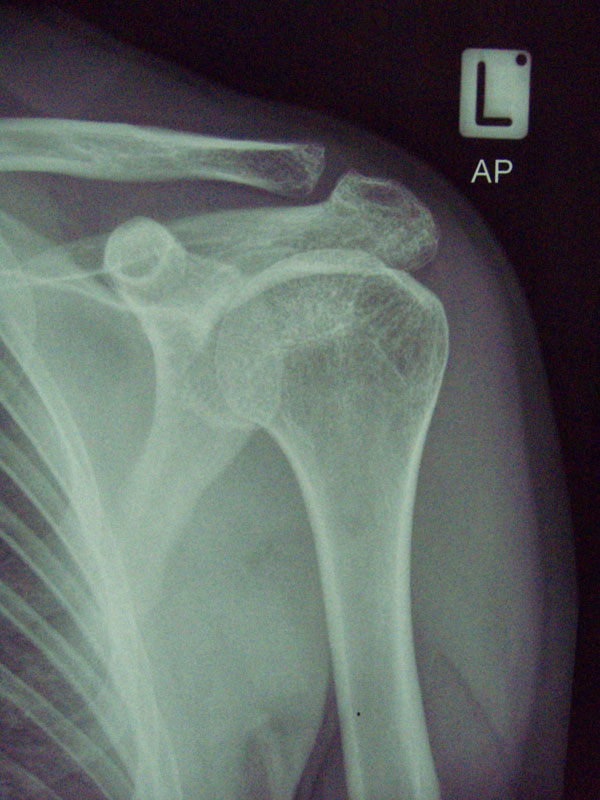

I’m having a Bankart repair done on my shoulder on Monday. Below are some photos of my shoulder. Uunfortunately you can’t see much damage as it’s the soft tissue which needs repaired. My shoulder pops out of the socket on a regular basis ever since I was body checked in a non-contact ice hockey game. I even managed to dislocate it picking up a bottle of coke the other day!